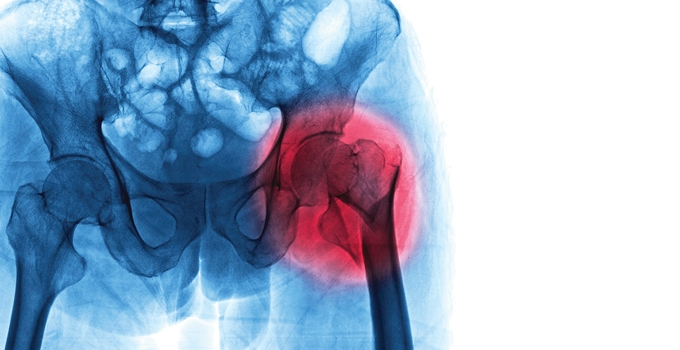

Rhumatologie

Rhumatismes : les douleurs restent insuffisamment prises en charge